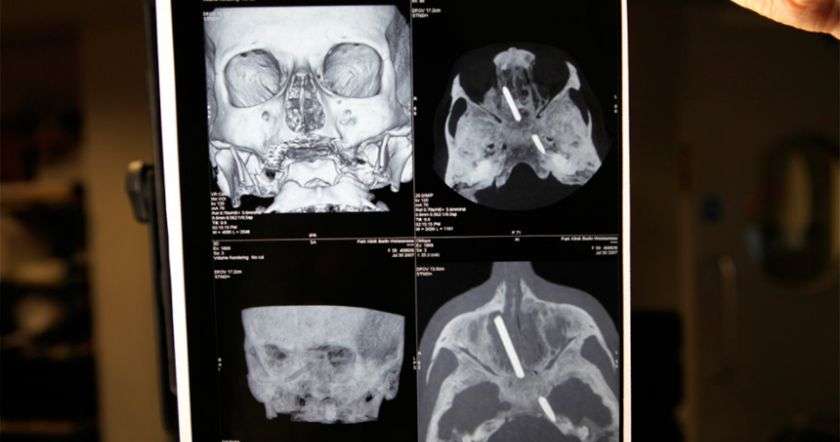

Серджио утверждает, что им удалось успешно восстановить позвоночник, нервы и кровеносные сосуды.

По словам Канаверо, операция была проведена его китайским коллегой Жень Сяопинoм при участии команды из Медицинского университета Харбина.